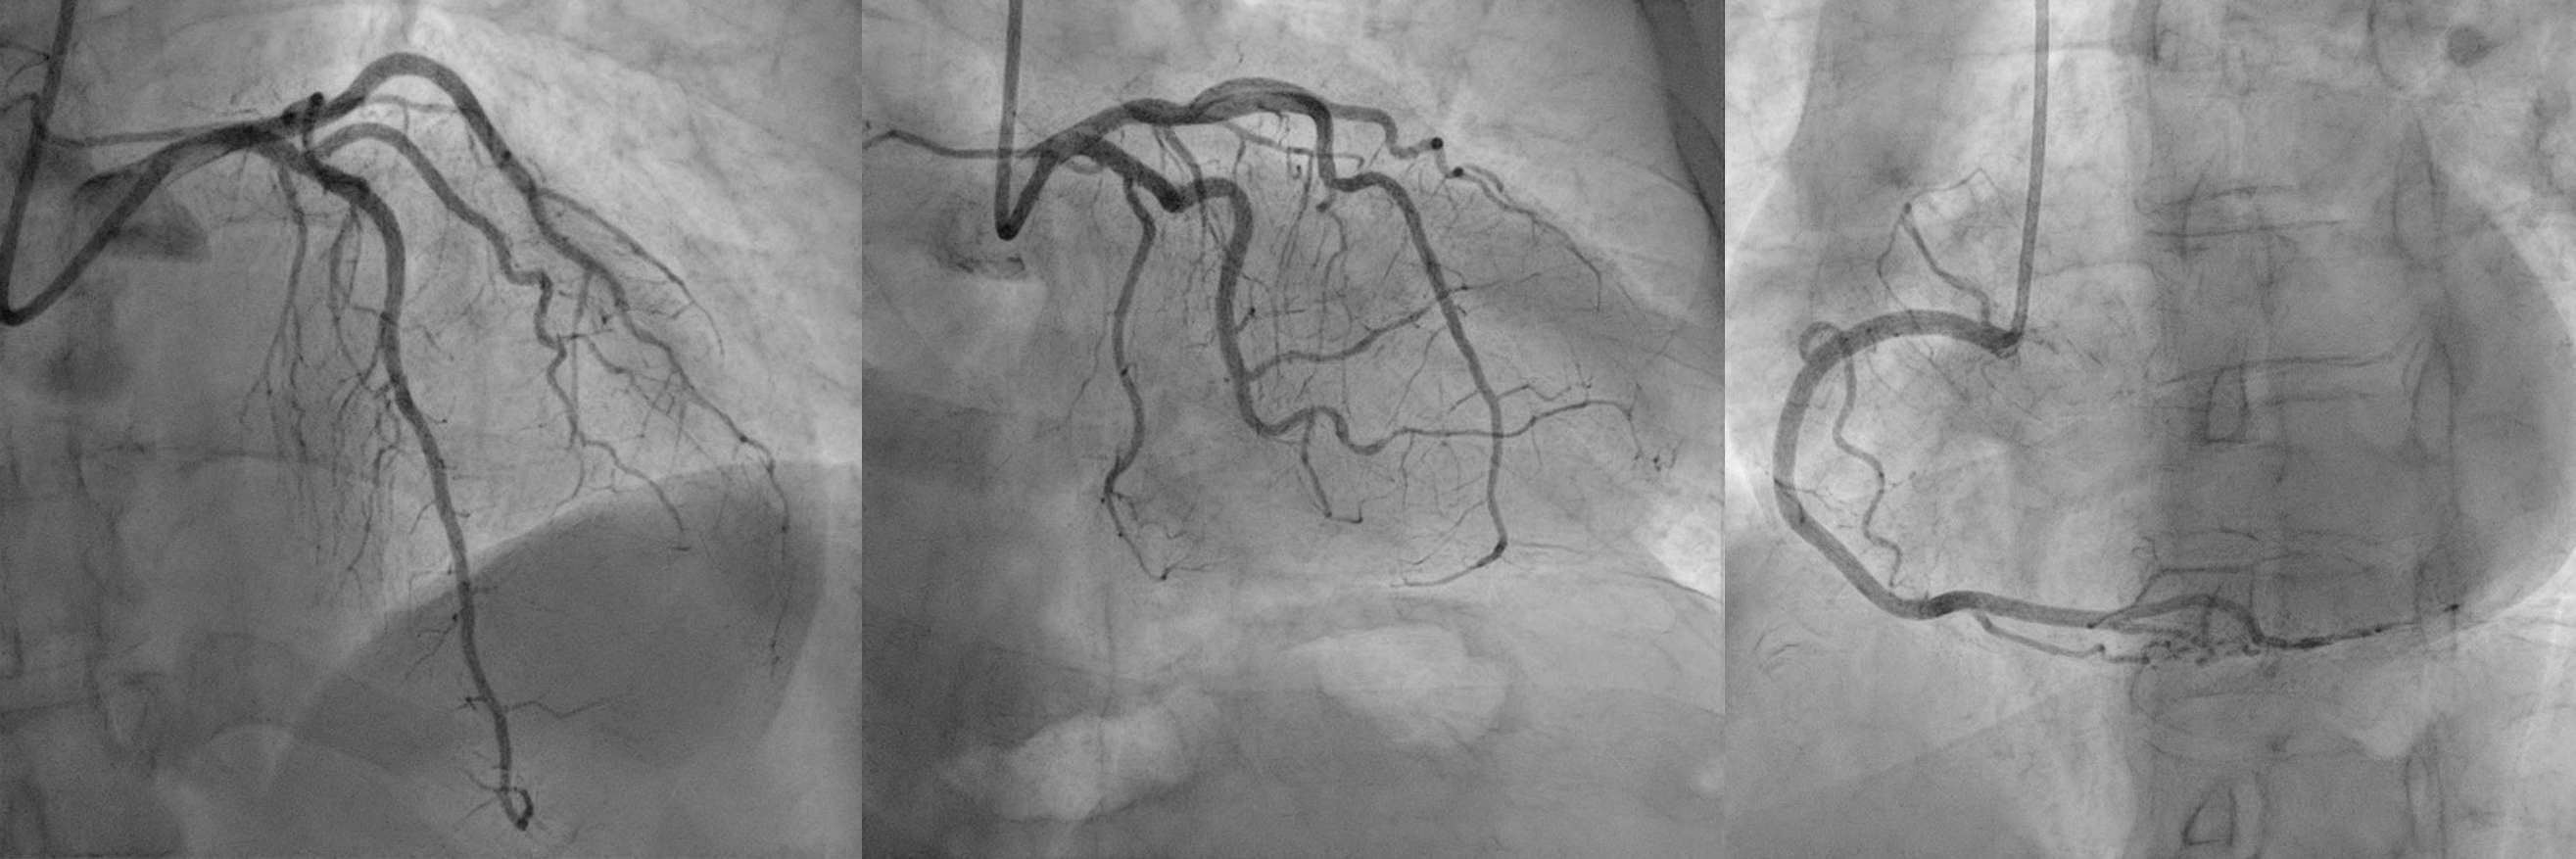

Upon admission to our center, the patient continued to experience precordial pain. She was hypertensive, normocardic, and showed no signs of heart failure. ECG showed ST-segment elevation in the inferior, anterior, and lateral leads. Emergency coronary angiography was performed after dual antiplatelet therapy and intravenous nitroglycerin were administered. At the time of the study, the patient was asymptomatic, ECG changes had resolved, and no significant stenoses were found.

Figure 2. Coronary angiography showed no obstructive coronary lesions.

Figure 2. Coronary angiography showed no obstructive coronary lesions. Figure 3. CMR findings: apical aneurysm, microvascular obstruction, and mural thrombus in four-chamber view (LGE). Lateral wall edema (T2 mapping) and intra-infarct hemorrhage (T2* mapping) in short axis at mid-ventricular level and three-chamber view.